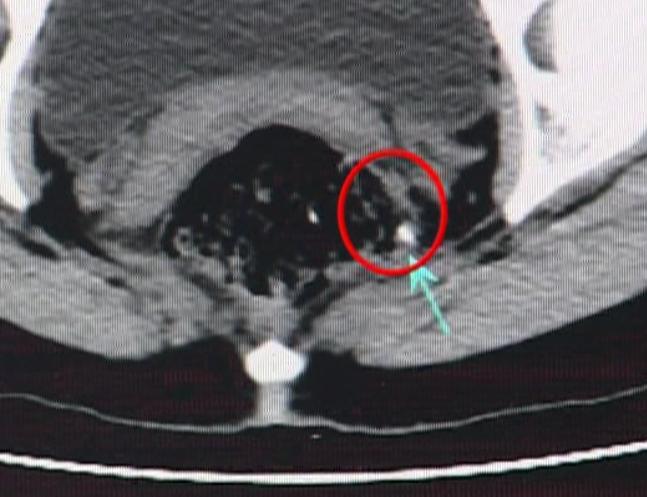

借助B超和CT治疗

医生终于在肛管2厘米的地方找到

这个米白色的异物

竟是一根完整的长约2厘米

粗2毫米的鱼刺